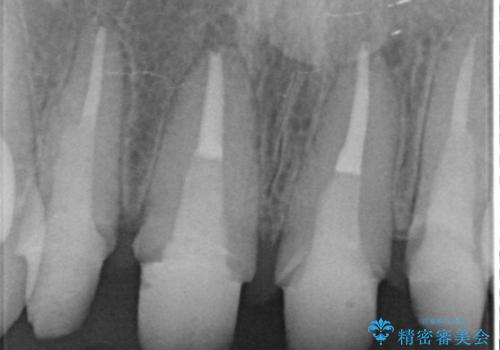

- 歯ぐきの黒っぽさ、暗い色調の前歯の改善を求めて来院されました。

金属を用いたコア・クラウンが装着されており、全ての金属を除去したのちのメタルフリー治療を計画します。

金属のフレームを用いるクラウンは色調が暗くなる傾向にありますが、セラミッククラウンに置き換えたことで自然な明るさ、審美性を取り戻すことができました。